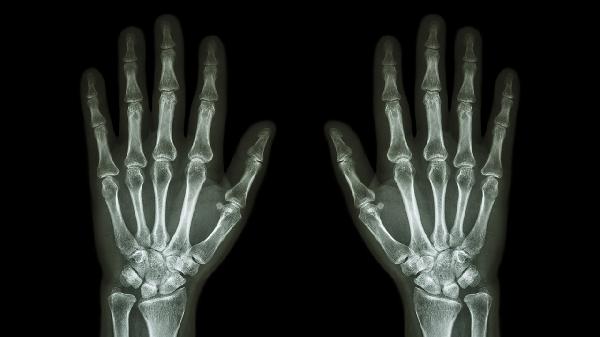

两手手指关节疼痛的主要原因有哪些

两手手指关节疼痛可能由骨关节炎、类风湿关节炎、痛风性关节炎、外伤或过度使用、腕管综合征等原因引起。

建议保持手指关节适度活动,避免寒冷刺激。均衡饮食中可增加富含欧米伽3脂肪酸的深海鱼类,适量补充维生素D和钙质。疼痛持续超过两周、伴随关节变形或全身症状时应及时就诊风湿免疫科或骨科,通过血液检查、X线或核磁共振明确诊断。日常生活中注意手指保暖,使用工具时分散受力,避免单指过度承重。